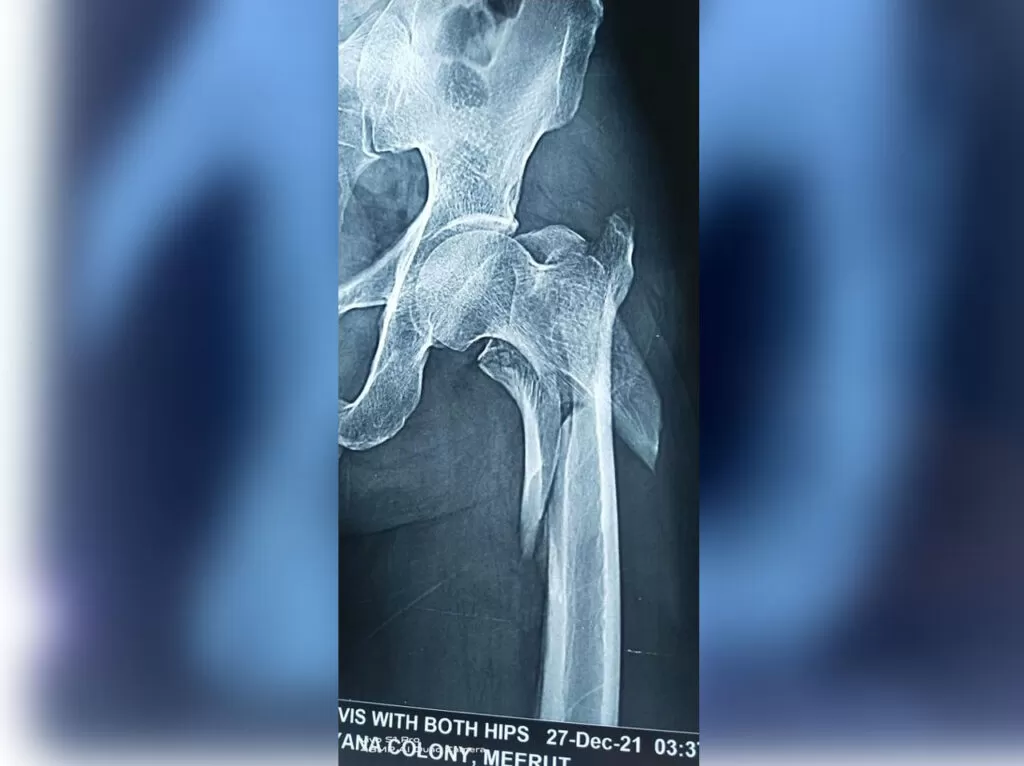

Mr. Iqbal

Name: Mr. Iqbal

Date of Operation: 31 Jan 2022

Age: 65 Years